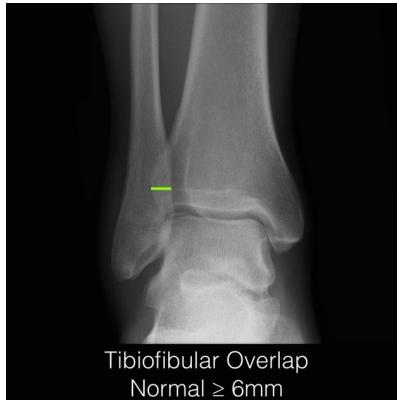

Tibiofibular Overlap

- Normal: ≥ 6 mm (AP view)

- Normal: ≥ 2.8 mm (mortise view)